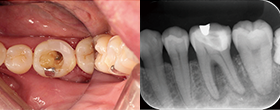

Case1 湾曲根管

• CC「左下奥違和感」主訴に来院

• 左下⑤6⑦Br除去→左下7 2次カリエス認める

• 湾曲大きく穿通せず…ハンドファイルで治療回数5回

EdgeSequel

Sapphire™#15/.06テーパーにてグライドパス形成

• 作業長確認

最終拡大#40/.04テーパー